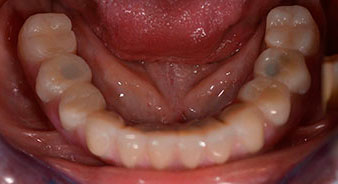

The impression and bite registration were then performed so that the dental technician could begin producing the provisional restoration immediately. This was then screwed in on the same day (Fig. 17 and 18).

Following the time required for the osseointegration, the final impression of the implants could be performed and the final denture produced accordingly (Fig. 19 and 20). At this point, the dentist and patient were able to decide together whether to use a ceramic or acrylic veneer and a zirconium or metal framework. In this case, Dr. Pascu’s team decided on an acrylic veneer based on the unclear prognosis for the maxillary dentition and the fact that tooth 24 is elongated. This type of veneer is generally considerably easier to adapt and can thus be subsequently altered to reflect the new situation in the maxilla.